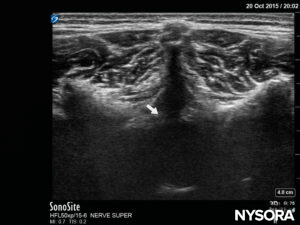

The spinous process of the targeted vertebral level should be identified by counting up from Tuffier’s line and by counting down from the most prominent C7 cervical vertebra (Figure 15). Preprocedural US imaging is performed with the probe in three planes: transverse (SAX), median sagittal (median LAX), and paramedian oblique sagittal (paramedian oblique LAX). The distance from the patient’s skin to the epidural space can thus be measured.In the SAX (Figure 16), the window between two spinous processes must be found, and the anterior complex of the vertebral column (posterior longitudinal ligament, anterior dura, and vertebral body) in the depth of the image will be the first structures to be identified. The posterior complex (ligamentum flavum and posterior dura) may be more difficult to visualize but will be approximately at the level of the lamina (Figure 17).

FIGURE 17. US image in the short-axis view, showing the posterior complex with the dura (white arrow).